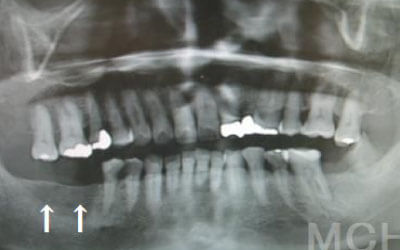

2 歯が傾いてくる、落ちてくる

歯は互いに支え合い、バランスを保っています。そのため、歯が抜けると支えがなくなり、抜けた部分の両隣の歯が傾いたり、上の歯が下に移動してきたりすることがあります。